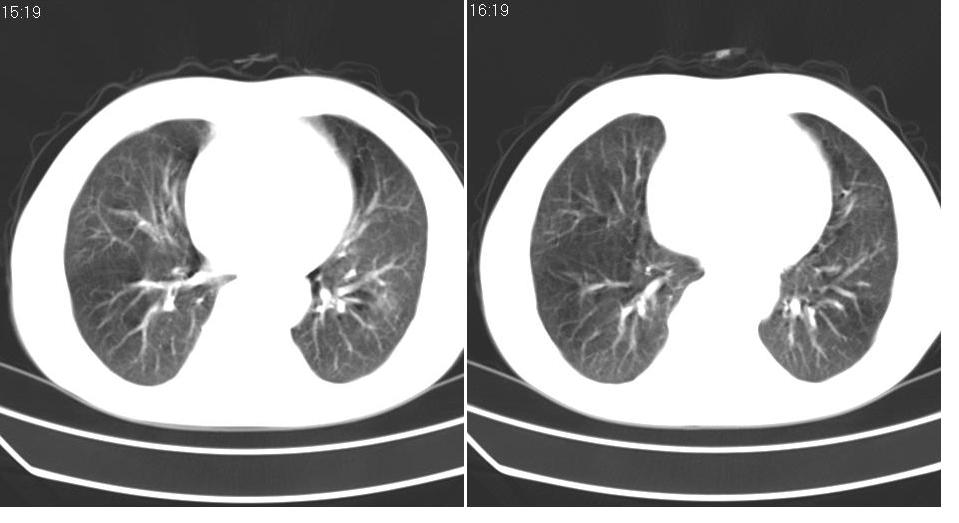

男 60岁,咳嗽,喀痰,胸闷,有吸烟史,正常图片未上传,请谅解。

左肺肿块有分叶、有毛刺,符合周围型肺癌。

考虑左肺下叶周围型肺癌可能性大。

分叶状肿块,有毛刺,有晕,有粗纹理直通肺门,支持考虑周围型肺癌